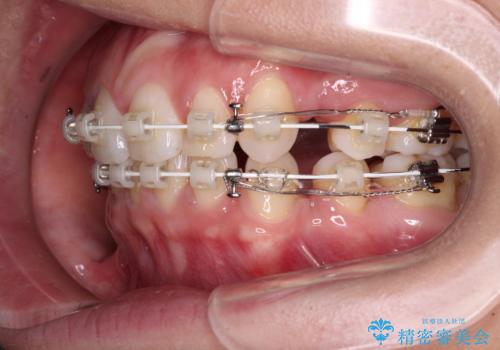

- 矯正装置

- 審美装置

- 治療期間

- 1年7ヶ月

- 治療回数

- 10-30回